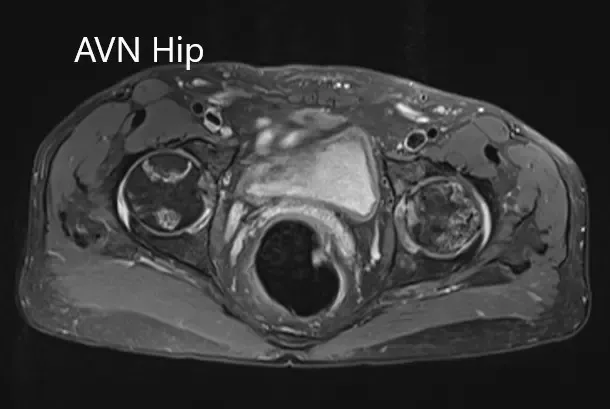

Secciones axiales de la T1WI y T2WI de la RM.

La cabeza femoral izquierda estaba colapsada con contorno irregular y muestra áreas de intensidad de señal alterada con una línea de demarcación. Zonas hipointensas tanto en T1WI como T2WI observadas en la cabeza sugestivas de esclerosis. Se observa edema de médula circundante. Una pequeña cantidad de derrame articular con pocos osteófitos observados. Se conservó el espacio de la articulación.

La cabeza femoral derecha muestra áreas de intensidad de señal alterada con la línea de demarcación serpiginosa visualizada; áreas hipointensas tanto en T1WI como T2WI se observan en la cabeza que sugieren esclerosis. El contorno femoral de la cabeza era normal. Se observa edema de médula circundante. Se observa un pequeño derrame articular. Se preserva el espacio articular.

El porcentaje de áreas necróticas en cabezas femorales bilaterales es aproximadamente del 60-70%.